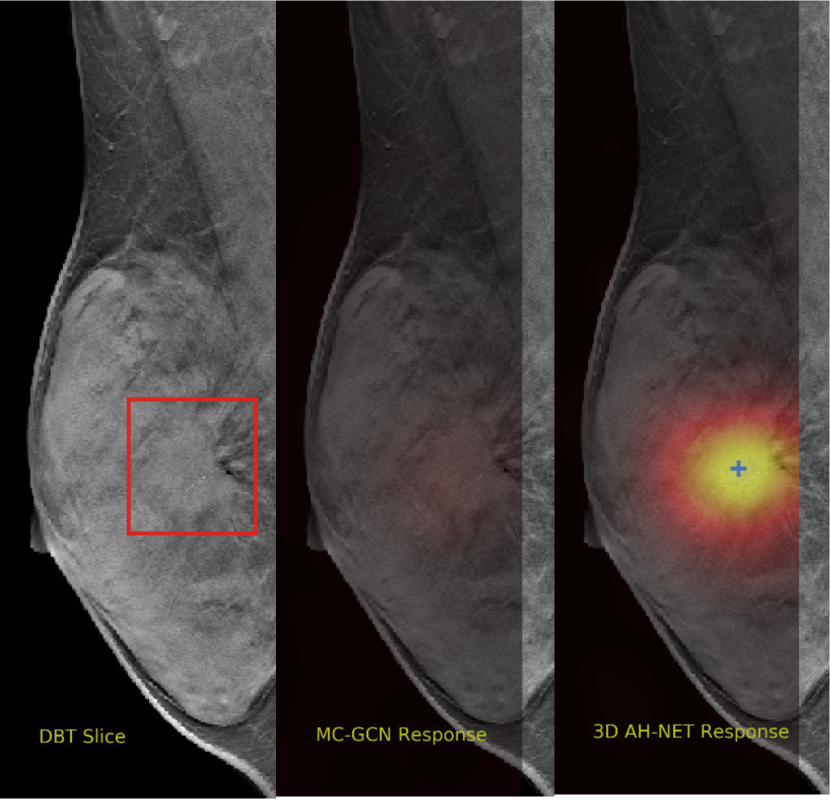

We selected some example slices from the DBT dataset to demonstrate the advantage of our proposed AH-Net for the Breast cancer screening. From Fig. 8 to Fig. 12, we show slices from five test DBT volumes that both the MC-GCN and the proposed 3D AH-Net could successfully detect the suspected breast lesion. The original DBT slice is shown on the left with the lesion annotated by our radiologist. Please note the original annotation is a 3D box. The figures in the middle and on the right are response maps from MC-GCN and 3D AH-Net overlaid on the original image, respectively. The detection locations obtained with non-maximal suppression are displayed with cross markers. As shown in the images, the proposed network can detect breast lesions varying in sizes and appearances. The confidence of the 3D AH-Net is usually higher than that of MC-GCN. From Fig. 13 to Fig. 17, we show five volumes that MC-GCN failed to detect the lesions since the lesions were not distinguishable from other breast tissues using the information within the slice. In contrast, 3D AH-Net was able to detect the lesions from such volumes using the 3D context between slices. As shown in Fig. 18 to Fig. 22, there are also volumes with lesions that both network failed to detect. Such lesions normally reside in the dense breast tissues. The boundary between these lesions and the normal breast tissues usually have low contrast. The networks sometimes also confuse them with other roundish structures in the breast such as lymph nodes or skin moles.

Refer to caption

Figure 13: Example DBT slice 6 with a lesion that can only be detected by 3D AH-Net. The lesion is highly blended within the dense breast tissues which makes it challenging for both the radiologists and the networks to detect through a single slice. In contrast, the lesion can be detected by considering the consistency of the structure across a few neighbouring slices.

Figure 14: Example DBT slice 7 with a lesion that can only be detected by 3D AH-Net. The lesion is highly blended within the dense breast tissues which makes it challenging for both the radiologists and the networks to detect through a single slice. In contrast, the lesion can be detected by considering the consistency of the structure across a few neighbouring slices.